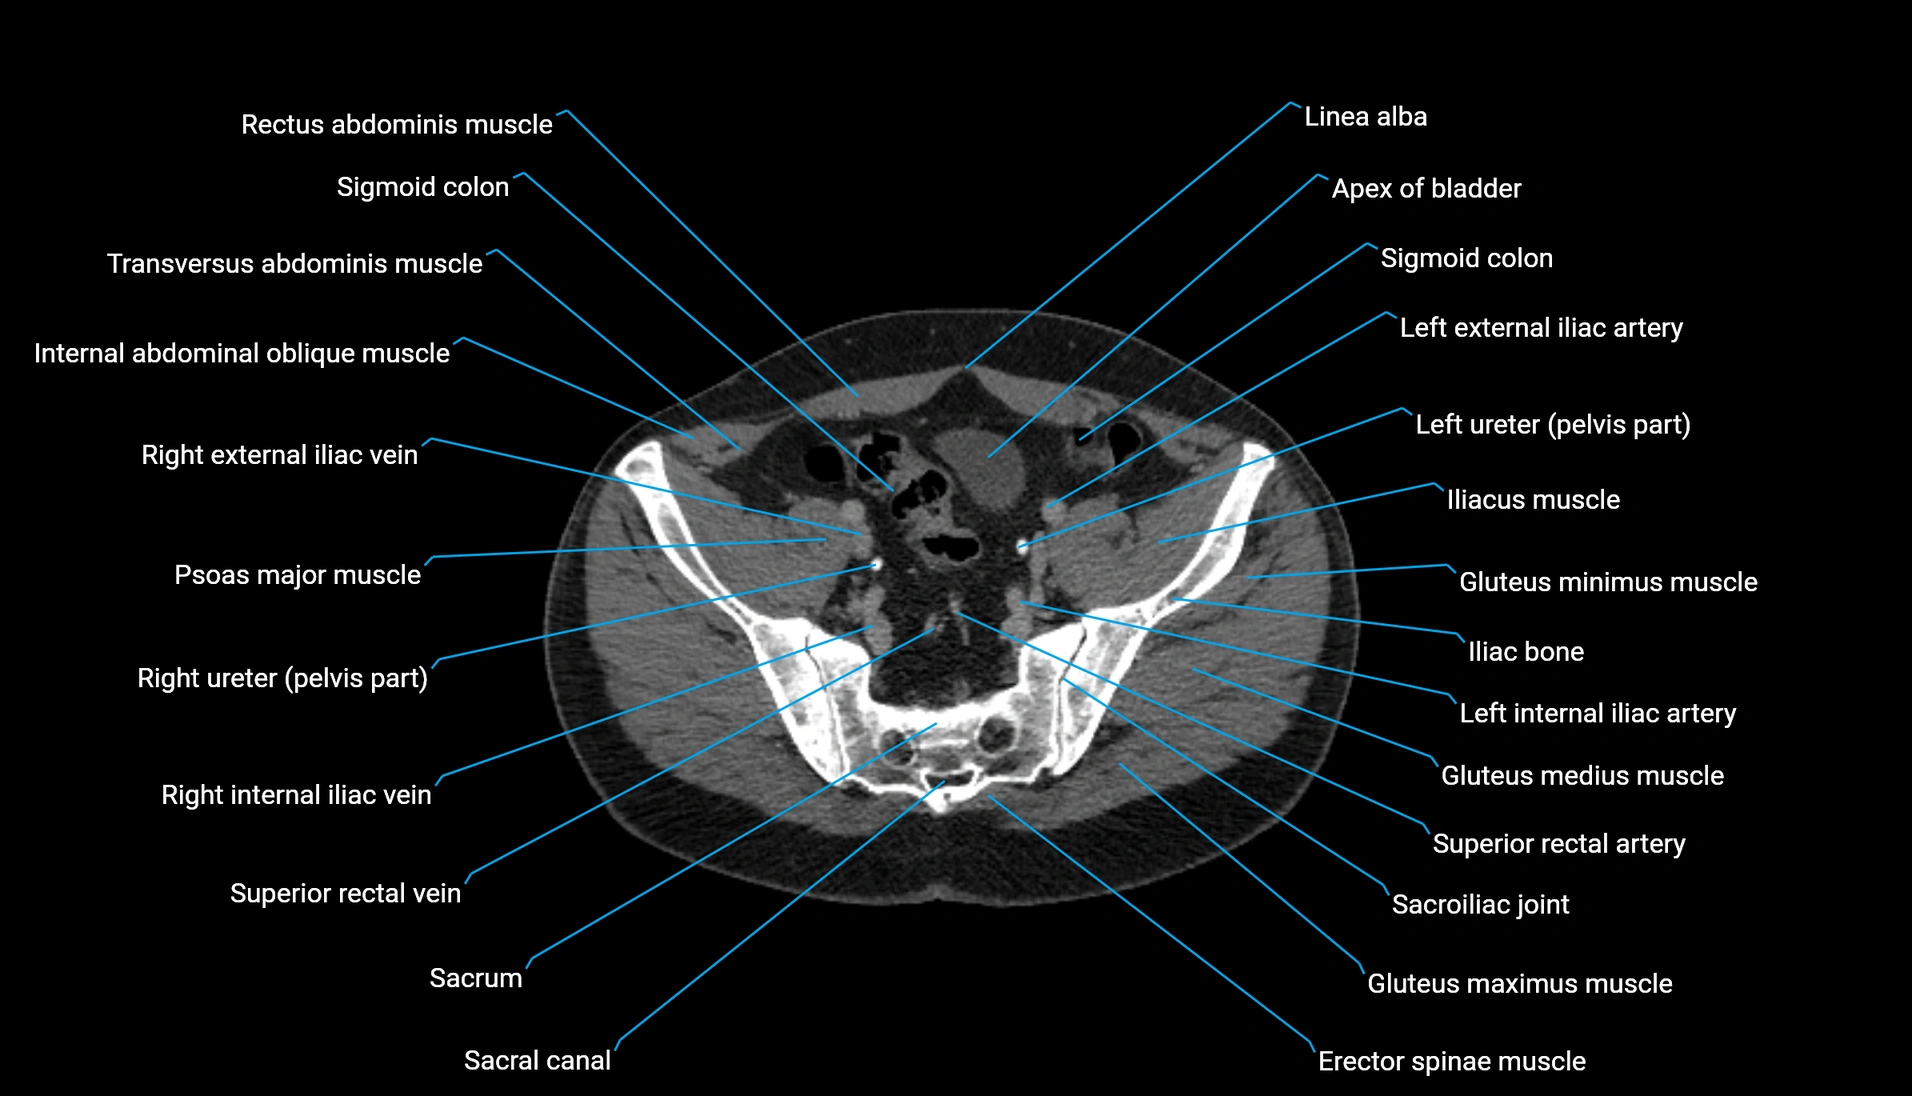

CT Appearance

Non-contrast CT:

-

Demonstrates cortical bone of acetabular rim in excellent detail

Detects fractures, dysplasia, retroversion, or bony overcoverage (pincer impingement)

3D reconstructions used in preoperative hip surgery planning

CT VRT 3D image

CT image